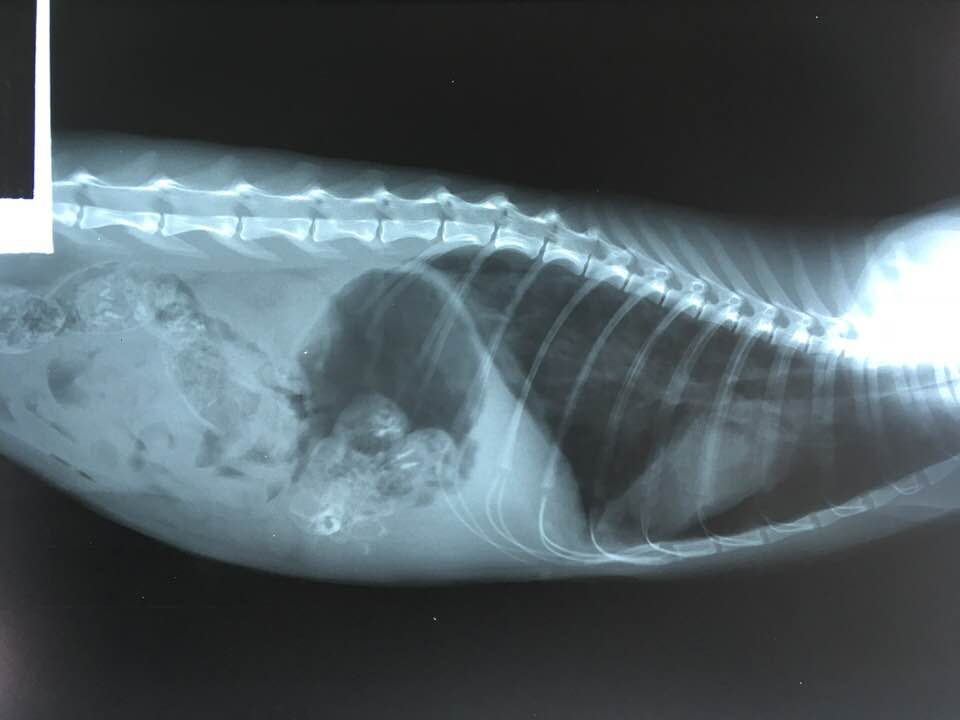

We hebben de mogelijkheid om digitaal röntgenfoto’s te maken van thorax, buik en bewegingsapparaat. We beschikken over een zeer goed echoapparaat voor het maken van echo’s van dracht en van de buikorganen. Mocht er uitgebreider onderzoek nodig zijn of een specialistische operatie dan onderhouden wij korte lijnen met laboratoria en specialistenklinieken zodat we u goed kunnen adviseren over waar u moet zijn. Al onze appparatuur wordt jaarlijks gekeurd en getest.